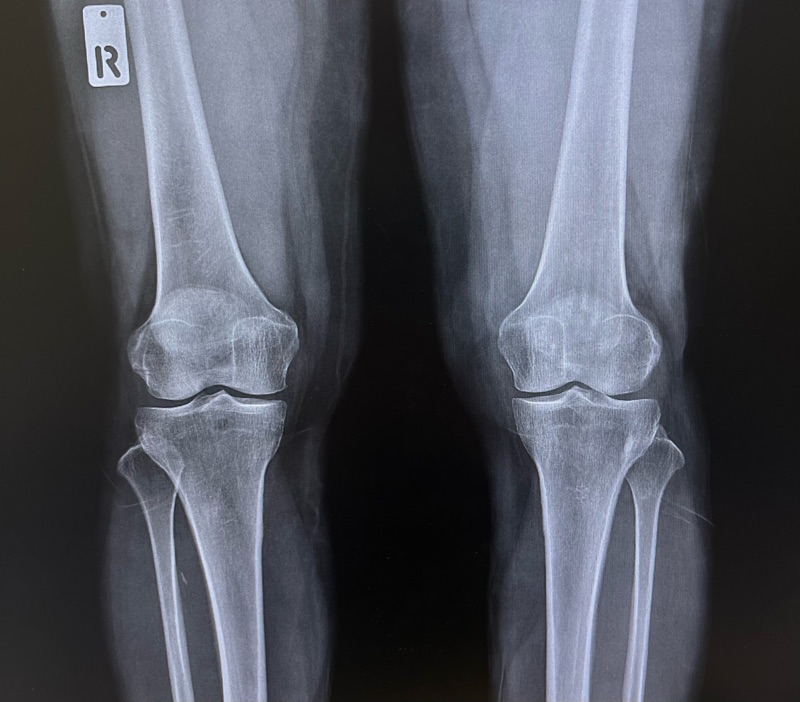

คุณศศิ อายุ 49 ปี เป็นแม่บ้านที่ต้องเดินขึ้นลงบันไดและยืนทำครัวทุกวัน เธอเริ่มปวดเข่าด้านใน ลุกขึ้นจากพื้นแล้วเจ็บจี๊ด ไปตรวจเอกซเรย์พบว่าเป็น เข่าเสื่อมระยะ 2

คือช่วงที่กระดูกอ่อนเริ่มสึกเพียงเล็กน้อย ผิวข้อเริ่มไม่เรียบ แต่โครงสร้างข้อยังดีมาก ช่องข้อยังไม่แคบจนผิดรูป และกระดูกยังไม่งอกผิดลักษณะ